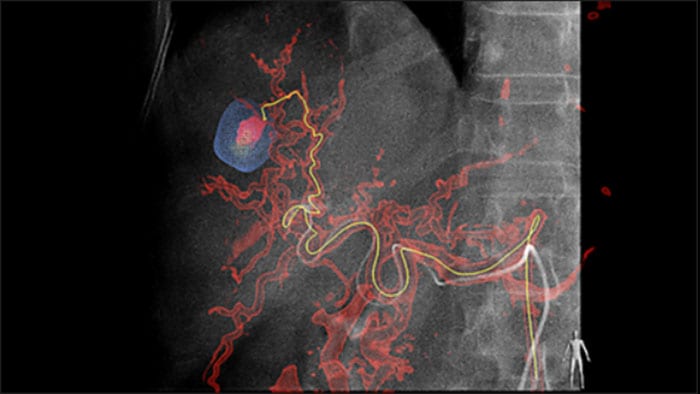

La solución de Detección automática de alimentadores puede mejorar, de forma significativa, la detección de arterias nutricias. EmboGuide le ayuda a maximizar la eficacia de sus procedimientos de quimioembolización transarterial (QET), ya que potencialmente mejora su sensibilidad, reduce los falsos positivos y maximiza la concordancia entre lectores1. EmboGuide también proporciona una guía 3D, en vivo, eficiente y basada en el flujo de trabajo con detección automática de alimentadores1.

La adopción de técnicas de quimio/radioembolización como la QET y la Radioterapia interna selectiva (Selective Internal Radiotherapy, SIRT) impulsa la necesidad de estandarización y eficiencia. Caso tras caso, debe localizar de manera confiable y uniforme los tumores, identificar todos los vasos nutricios y planificar/llevar a cabo el enfoque intervencionista apropiado. Nuestra solución de Detección automática de alimentadores puede mejorar, de manera significativa, la detección de arterias nutricias en comparación con la TC de haz cónico sola. EmboGuide le ayuda a maximizar la eficacia de sus procedimientos de QET, ya que potencialmente mejora su sensibilidad, reduce los falsos positivos y maximiza la concordancia entre lectores.1

La capacidad de detectar y de distinguir nódulos hepáticos e identificar los vasos minúsculos del alimentador es fundamental para determinar el tratamiento apropiado. Navegar a la región de interés y llegar a todos los alimentadores, sin dejar de ser selectivo con la lesión, aumenta la oportunidad de éxito. La confirmación del punto final del tratamiento y el éxito de este mientras el paciente está todavía en la mesa incrementa la confianza en los resultados clínicos.